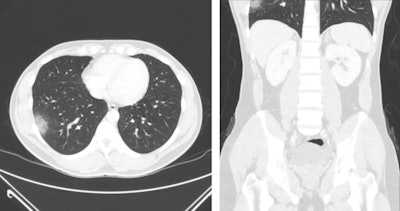

A 33-year-old man presenting with right lower quadrant abdominal pain, found to have acute appendicitis on abdominal/pelvic CT. Axial (left) and coronal (right) views on lung windows demonstrate focal peripheral ground-glass opacity in the right lung base. Images courtesy of the RSNA.